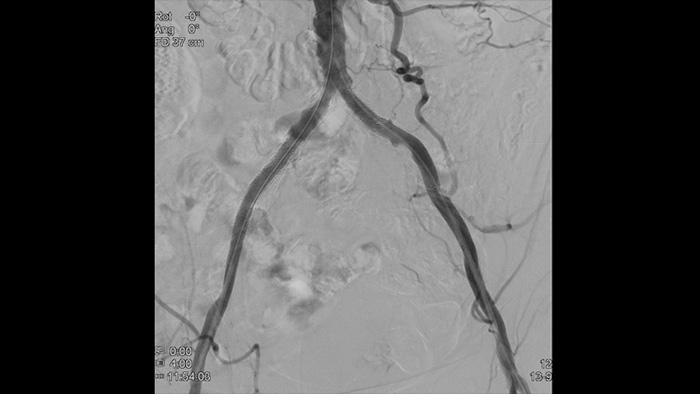

Angiografía por sustracción digital (ASD) 2D con tecnología ClarityIQ

ASD 2D con ClarityIQ

Visualiza imágenes de alta definición de los vasos con un detalle vascular excepcional para apoyar las estrategias de tratamiento precisas, la navegación y el seguimiento.